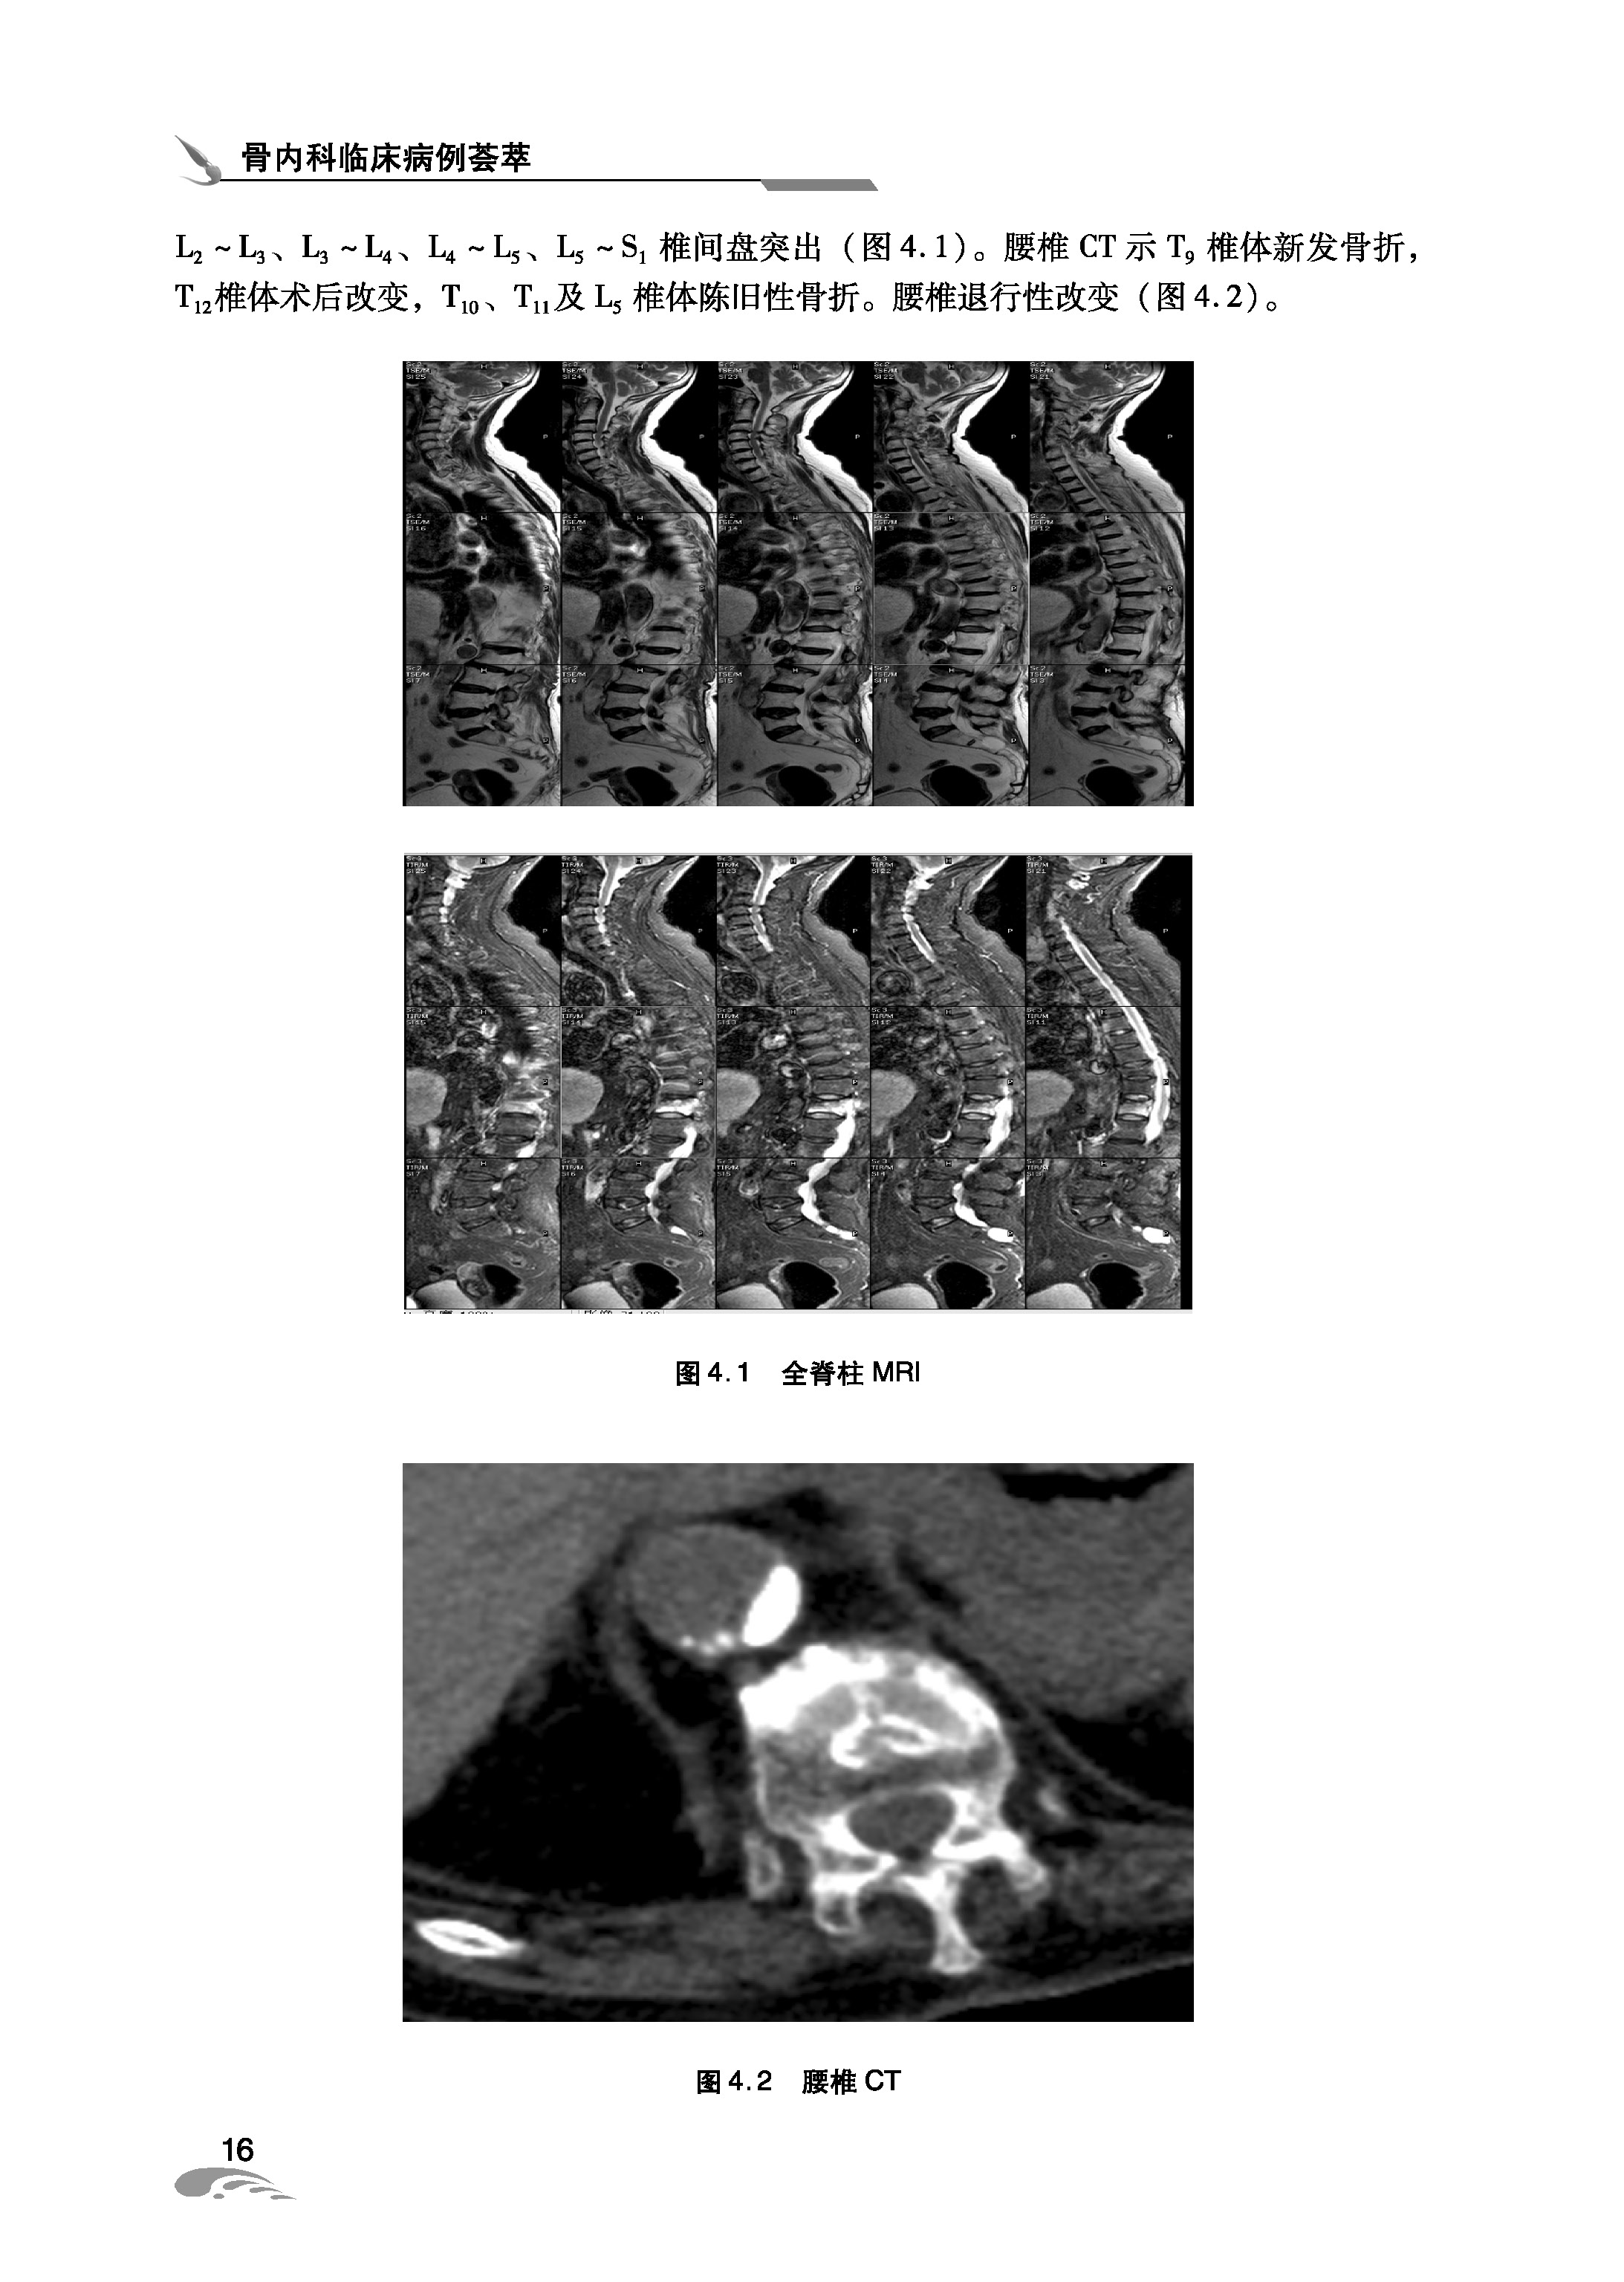

096 腰椎间盘突出症一例